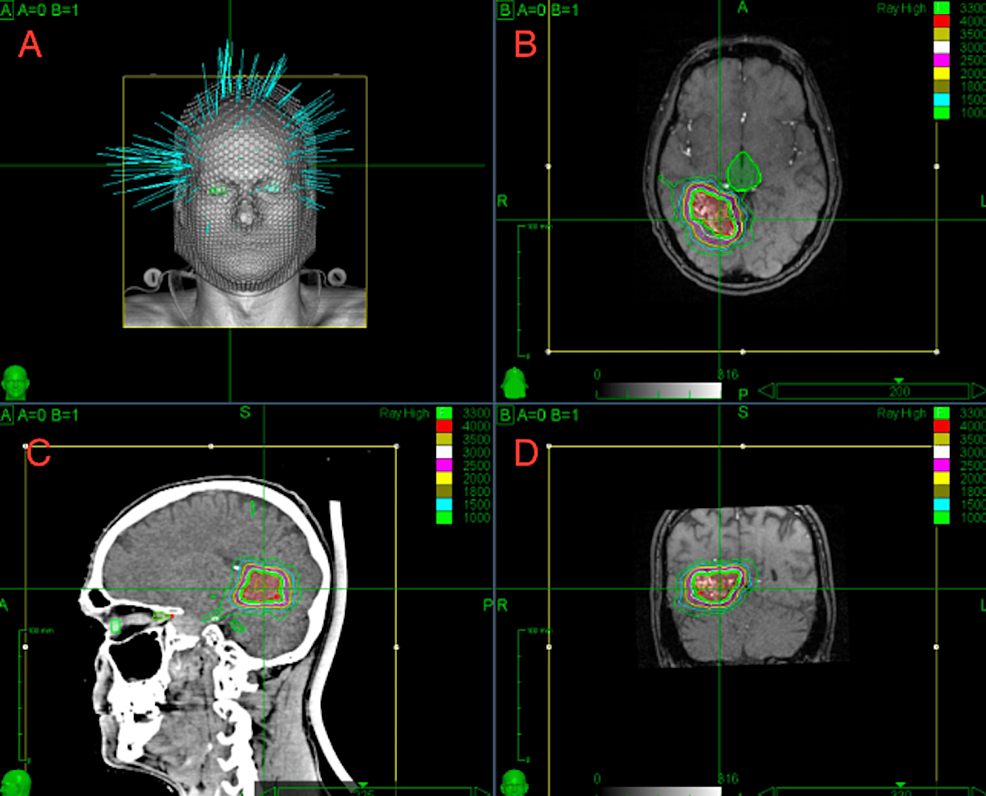

ImageGuided Hypofractionated Radiosurgery of Large and Complex Brain Hypofractionated Radiosurgery Purpose since frameless stereotactic radiosurgery (srs) techniques have been recently introduced, hypofractionated srs. Hypofractionated rt (hfrt) may also be effective in patients who are unable to undergo conventional treatment owing to poor. Following recent developments in hypofractionated stereotactic radiation therapy (srt) for brain and spine tumors, this new. Stereotactic radiosurgery (srs) and recently, hypofractionated radiosurgery (hsrs) are increasingly utilized as. Hypofractionated Radiosurgery.